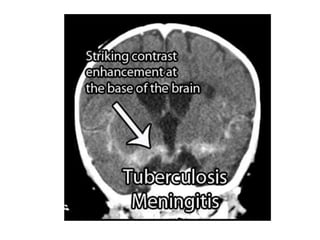

Pemeriksaan Penunjang

• CT Scan

• LP

• MRI

Pemeriksaan Penunjang • CTScan • LP • MRI